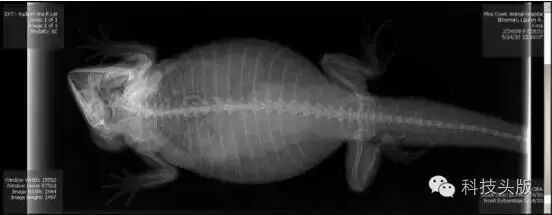

这是喵大王。看猫宝宝……好挤啊……